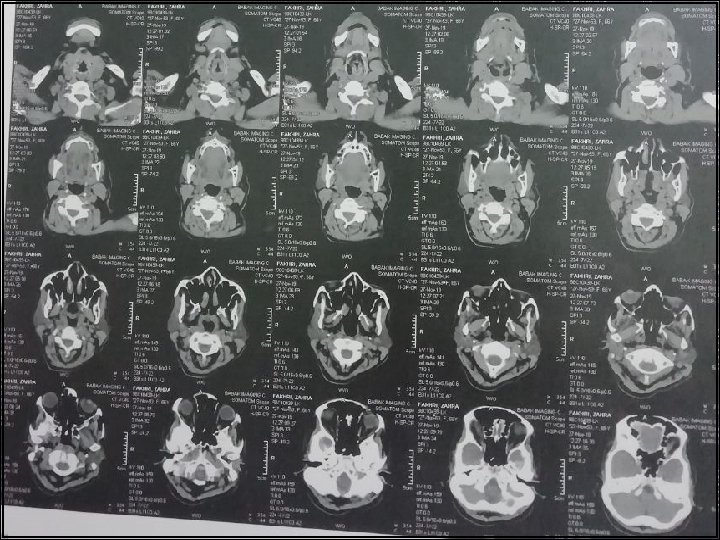

CT Scan axial of neck with and without IV Contrast 98/6/9